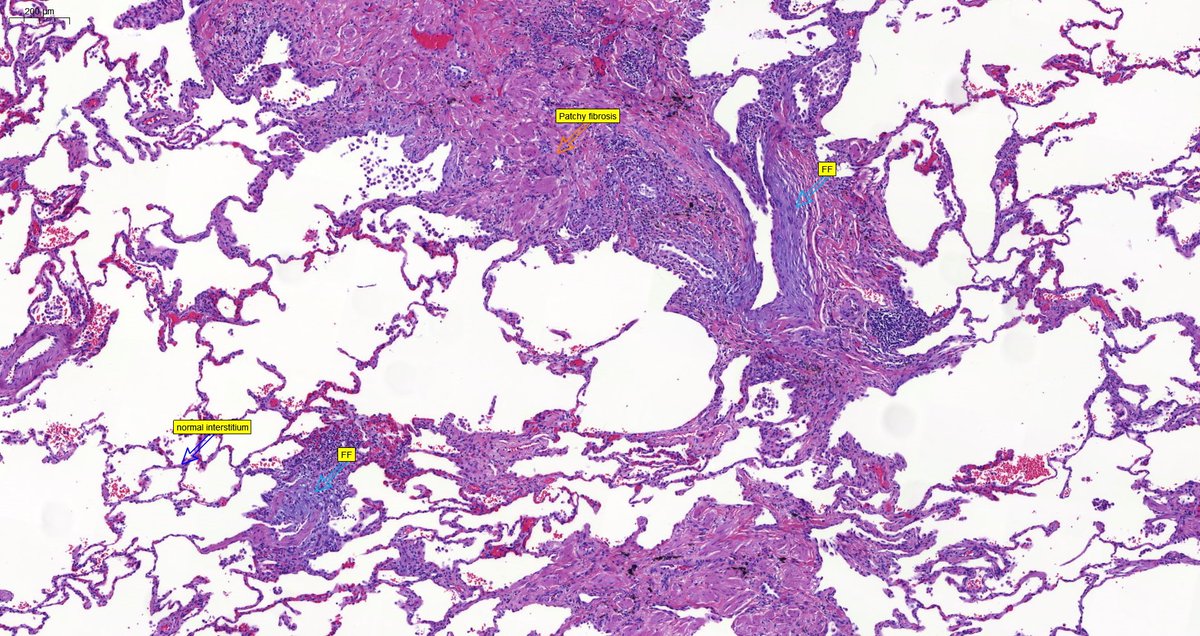

Usual Interstitial Pneumonia shows peripheral, lower predominant fibrosis in the #grosspath by @_Romo_Navarro Microscopically you can appreciate patchy fibrosis, fibroblastic foci & honeycomb #pulmpath #explantsRawesome #transplantpath #ILD